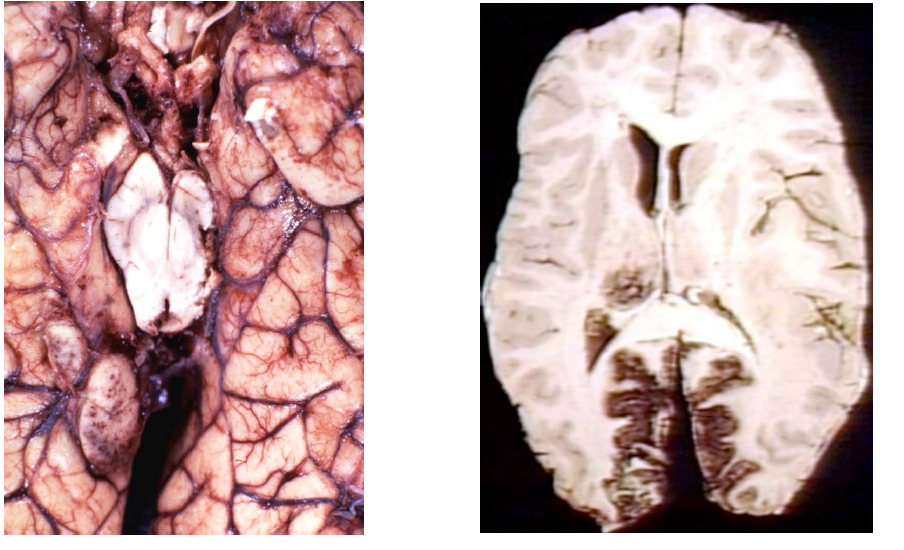

What is this process? How can you differentiate it from viral encephalitis?

Vasculitis

• May be part of a systemic vasculitis or isolated to the CNS.

• Requires transmural vessel wall inflammation

17 year old out parting at Elich’s and then got gastro and is overweight on OCPs. Presents with seizure then rapid decline.

Wa happened?

Venous Sinus Thrombosis

• Venous congestion over the convexities with parietal petechial hemorrhages.

Associated with:

– Post-partum

– Dehydration

– Hypercoagulable states

– Adjacent inflammation

(e.g., mastoiditis).